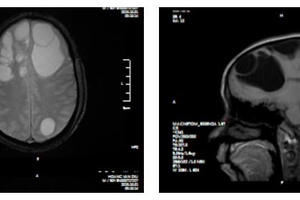

Ổ sán khổng lồ cư trú trong não khiến người đàn ông ở Phú Thọ mất dần trí nhớ, phù não diện rộng, phải phẫu thuật khẩn cấp.

Một nam thanh niên 35 tuổi sau nhiều năm nghiện món tiết canh đã nhập viện trong tình trạng hôn mê, phải mổ cấp cứu do bị sán “ăn” não.

Mấy ngày gần đây, cộng đồng mạng chia sẻ các bức ảnh chụp X-quang rất khủng khiếp của một bệnh nhân nhiễm sán. Theo đó, trên các bức ảnh X-quang là la liệt các xác sán xơ mít có đầu vôi hóa hình như hạt gạo. Theo các bác sĩ, nguyên nhân bị nhiễm sán là do ăn phải thức ăn sống như rau sống, tiết canh, gỏi cá… có nhiễm trứng, ấu trùng sán.